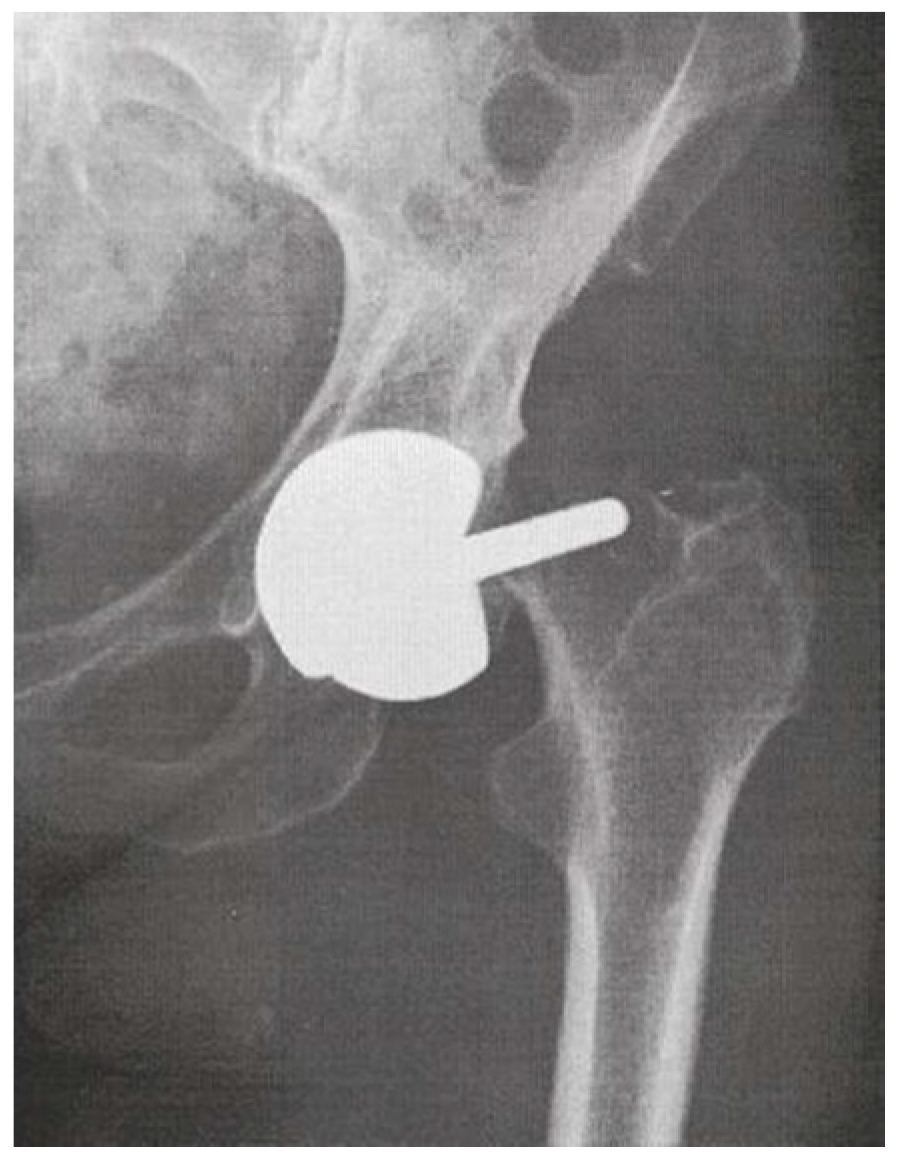

Early HRA failure modes mainly consisted of femoral neck fractures [11] (Figure 2), treated by revising only the femoral component and preserving the acetabular component and the MoM bearing. Large diameter MoM femoral heads modularly fitting on a prosthetic femoral stem had been specifically designed for these femoral component-only revisions of HRA (Figure 3). Following the good initial results of the Metasul® MoM hips and the reduced risk of dislocation with large diameter femoral heads, these HRA revision big femoral head (BFH) components were also used for primary THA, despite the smaller coverage angle of the acetabular design, the introduction of an additional MoM articulation at the taper–trunnion head–neck junction and despite the fact that these components had not been thoroughly tested for this indication [12,13].

Figure 2.

Early failure of an MoM HRA due to femoral neck fracture.